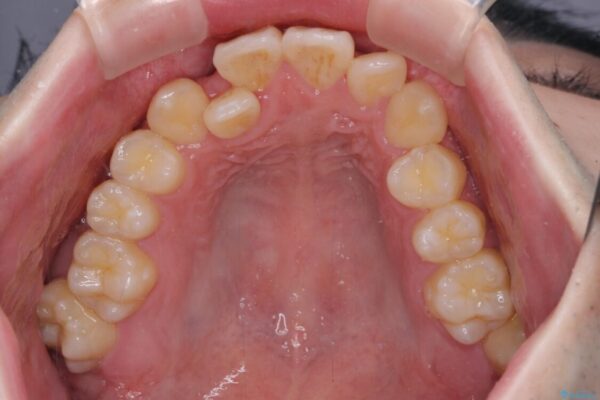

八重歯や奥歯の噛みにくさを気にして来院された患者様です。

前歯のクロスバイトや八重歯の他に、左右最後臼歯のシザーズバイト(鋏状咬合)が認められました。

治療前

• 全顎的なクロスバイト 補助装置を用いてワイヤー矯正 治療前画像